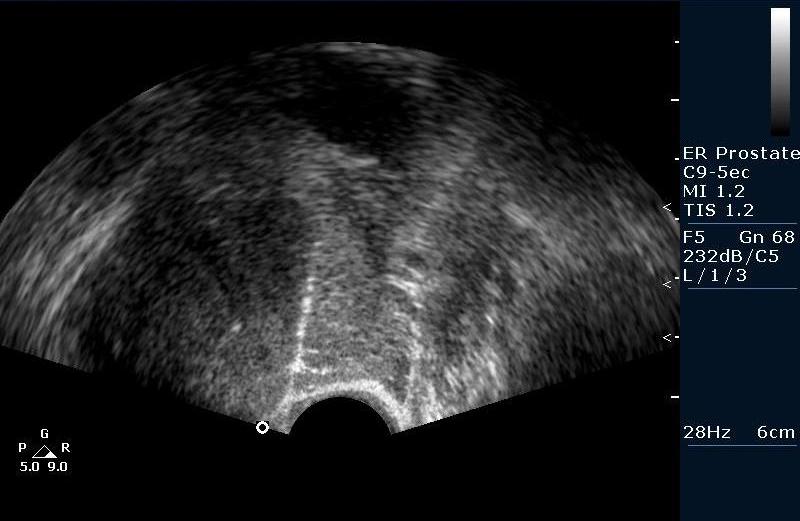

Биопсия предстательной железы под контролем Ультразвуковой визуализации. Рутинная практика в нашем отделении pадиологии, выполняется практически всем пациентам с повышенным уровнем ПСА (естественно, учитывая результаты осмотра урологов).

Биопсийная игла в железе (трепан биопсия)